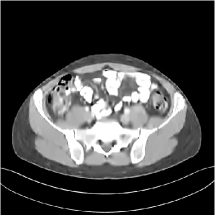

We firstly hand-tuned the reconstruction parameters () for one test slice and treated this set of parameters as the baseline. Similar to the PWLS-EP algorithm, we could determine the optimal (in terms of optimal RMSE) parameters for other testing slices by tuning the base parameters in a small range. However, we found that the change in reconstruction quality by picking a common set of parameters instead of slice-wise optimized parameters is quite small (only 0.2 HU in RMSE and without the loss of details). Therefore, the same set of parameters (baseline parameters) were used across testing cases and shown to be effective over the cases. In particular, we selected slice 48 of the XCAT phantom as the case for parameter tuning and set the regularization parameters (after tuning over ranges of values) as , , for ST, , , , , for MARS2, , , , , , , for MARS3, , , , , , , , , , , for MARS5, and , , , , , , , , , , , , , , for MARS7, respectively. In Fig. 14 in the supplement, we give the reconstructions for slice 48 of the XCAT phantom with various methods. Figs. 4 and 5 here show the reconstructions for two independent test cases (slice 20 and 60 of the XCAT phantom). Both of them used the same set of parameters obtained for slice 48. The zoom-in regions give an explicit comparison between the multi-layer sparsifying transform models and other methods such as FBP, PWLS-EP, and PWLS-ST. PWLS-MARS achieves better noise reduction and higher contrast.

Figs. 8, 9, 10, and 11 show the reconstructions of the four independent slices using the FBP, PWLS-EP, PWLS-ST, PWLS-MARS2, PWLS-MARS3, PWLS-MARS5, and PWLS-MARS7 schemes, respectively. Additional Mayo Clinic experimental results of the parameter tuning case (Fig. 15) are shown in the supplementary document. Table 1 lists the RMSE and SSIM values of reconstructions of the four independent test slices, with the best values bolded. Generally, the five and seven layer models provided the best RMSE and SSIM values. They outperform the single-layer model by HU in RMSE on average. However, the MARS5 and MARS7 models perform similarly. In order to strengthen the benefits of the multi-layer model, Table 2 lists the RMSE of the reconstructions in four different ROIs (shown in the reference of Fig. 11) with seven methods for slice 100 of patient L506. By observing the reconstructed images, we see that although the ST model achieves a cleaner reconstruction result than FBP and PWLS-EP, it still sacrifices some sharpness of the central region and suffers from loss of details. The deeper models have a somewhat more positive effect in terms of maintaining subtle features, which is clearly more essential to clinical diagnosis. Furthermore, as we will discuss later, after considerable parameter tuning, we found that the information contained in residual maps is gradually decreased with the number of layers, eventually vanishing at some layer, which suggests that very deep unsupervised models might not offer significantly better image quality.